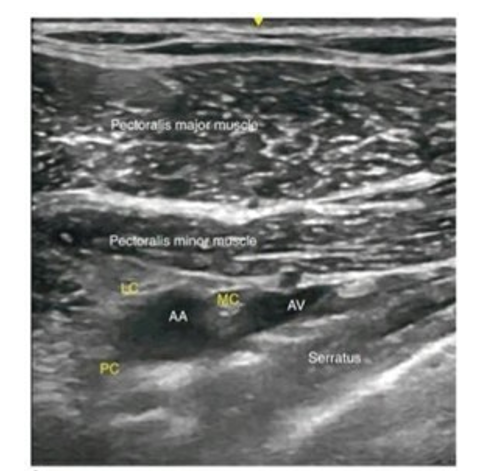

Under all aseptic precautions and patients in supine position, their head turned away from the side to be blocked and arm abducted at 90°. The high frequency probe of ultrasound machine (8-12 MHz) was positioned in parasagital plane just medial to coracoid process and inferior to clavicle.

After locating Axillary artery and vein just beneath sheath of pectoralis minor muscle and medial ,lateral and posterior cords appearing caudal , cephalic and posterior to the artery , respectively are located.

Ultrasound Image of Infraclavicular Brachial Plexus AA-Axillary Artery, AV-Axillary Vein, LC-Lateral Cord, PC-Posterior Cord, MC- Medial Cord